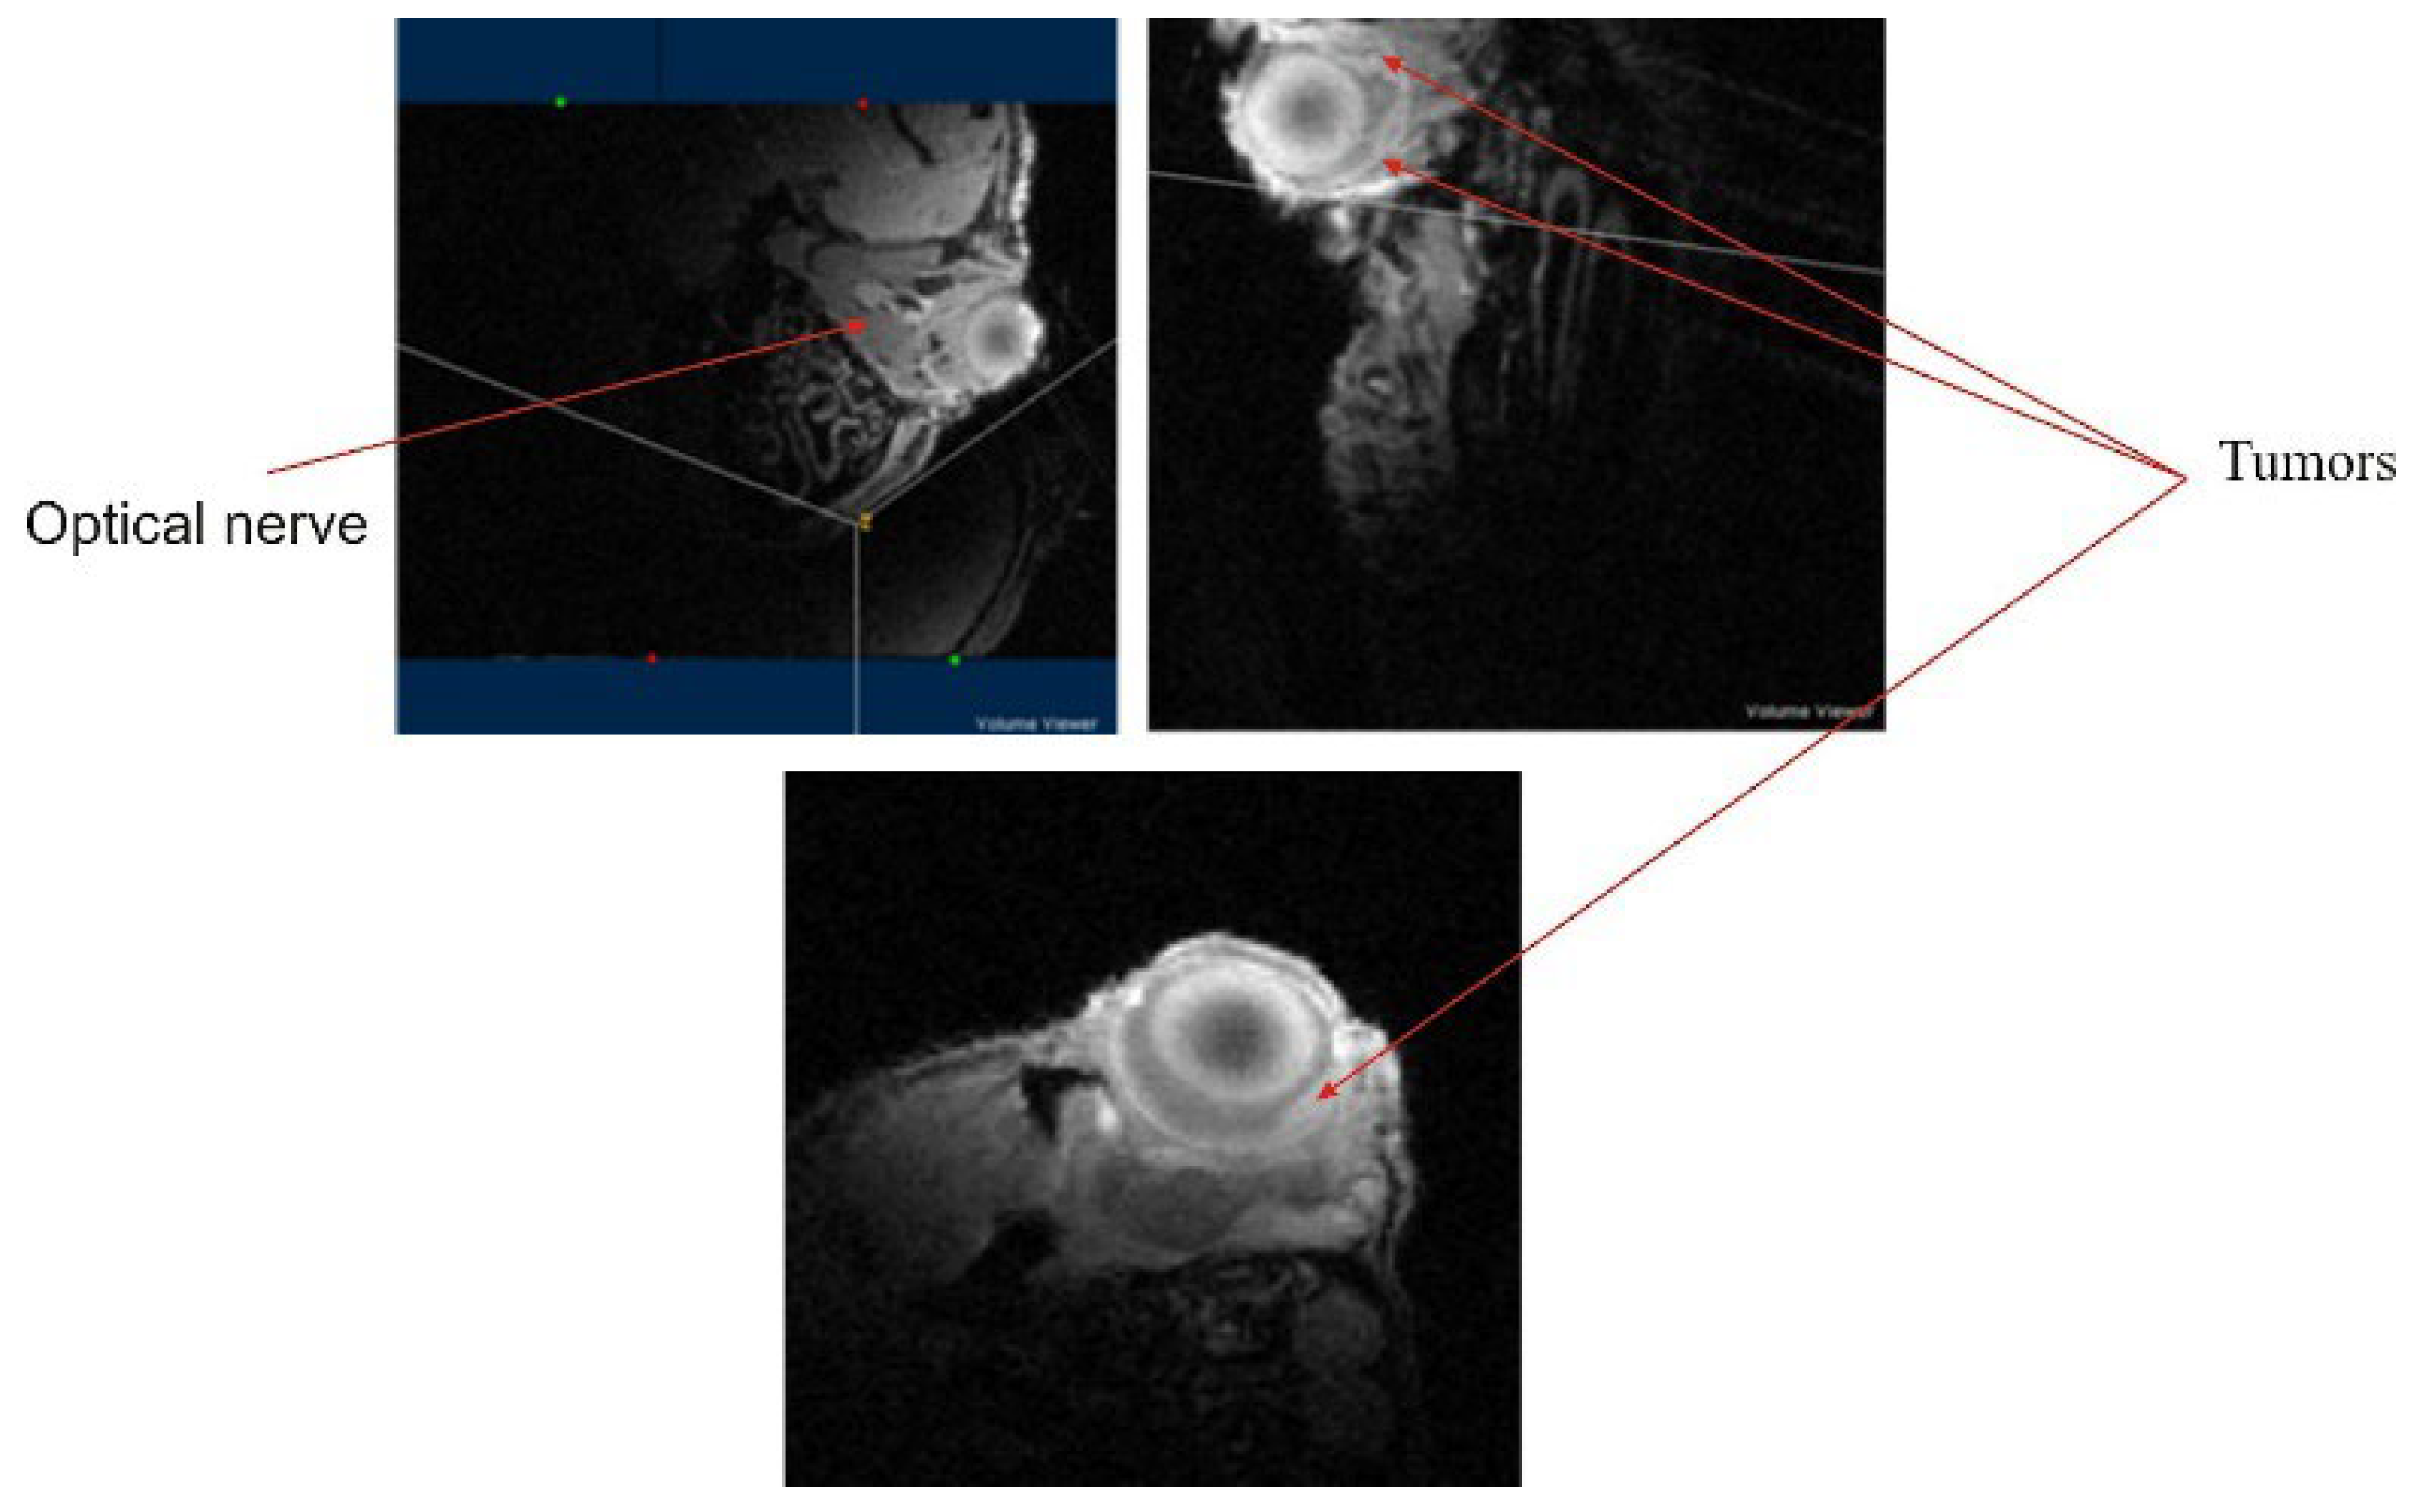

Finally, imaging on the mouse eye, an organ with a diameter of 3 mm, shows that early development of tumors in the retina could be characterized with good signal to noise ratio and resolution (Figure 13).

Figure 13. Results obtained with the resonant system presented in this work. An echo-gradient 3D image with the resolution of 100 μ3 (FOV 25 × 25 × 12.5 mm, data matrix 256 × 256 × 128) was acquired in about 40 min. The tumors developing in the retina layer are easily observable without contrast agents.